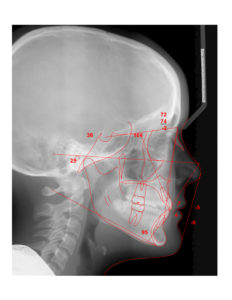

An 11.3 year old caucasian female presents with a chief concern that “my teeth don’t come together.”